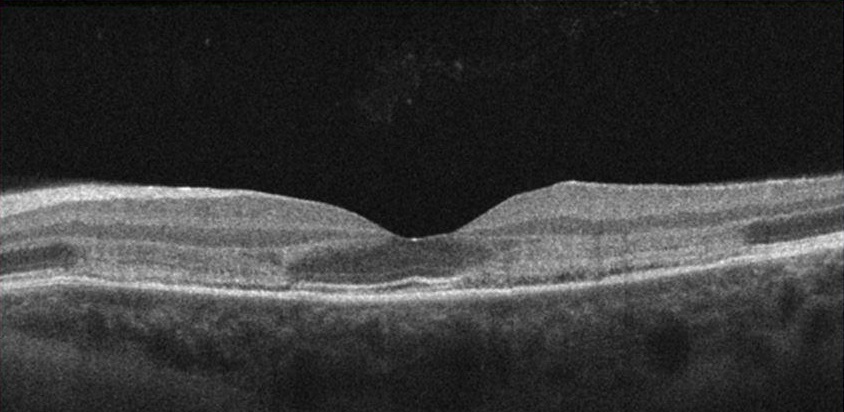

AMN in 22 year old female that presented with bilateral paracentral scotomas and blurry vision. Presenting BCVA was 20/20 OD and 20/25 OS.

Left eye: